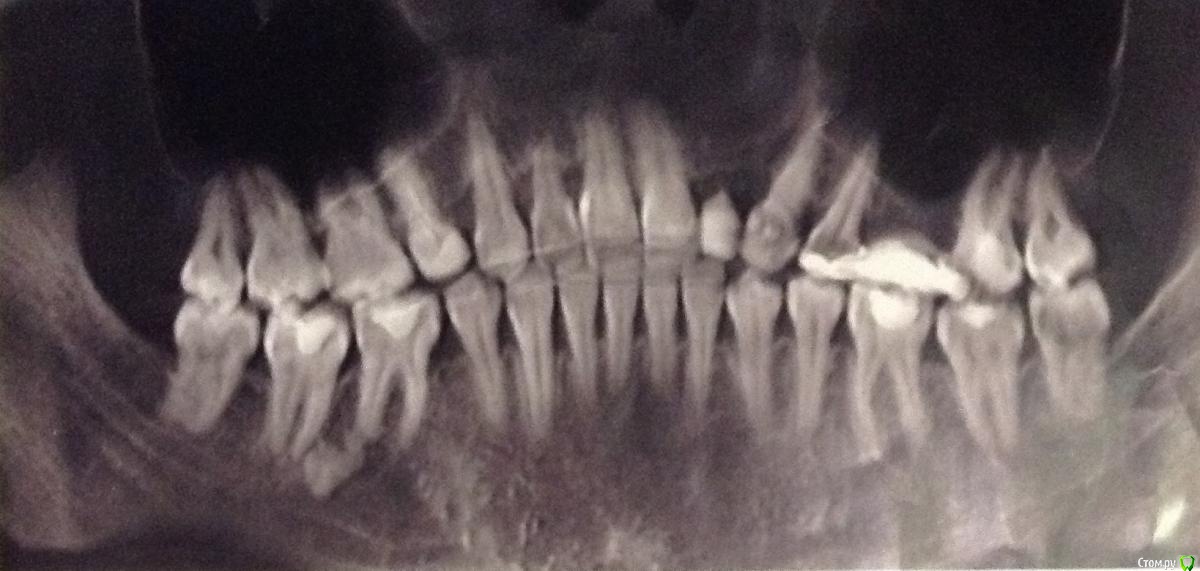

TFlow Опубликовано 29 сентября, 2018 Поделиться Опубликовано 29 сентября, 2018 Здравствуйте! Была сегодня на чистке зубов и врач сказала, что прямо за моими обеими нижними восьмёрками "просвечивает" кость. Она показала мне это в зеркало. Сказала, что видит такое первый раз в жизни (стаж 15 лет). Восьмёрки, как вы поняли, на месте (все 4), а слизистой за ними нет. На ортопантомограмме видно, что у меня в общей картине убыль кости. Это первый врач, который заметил, что видно кость за 8-ми, хотя последний раз зубы в этом году уже чистили, но другой доктор. Как-то страшновато. Что с этим делают? Зашивают или как? Ссылка на комментарий

TFlow Опубликовано 30 сентября, 2018 Автор Поделиться Опубликовано 30 сентября, 2018 (изменено) 106% что это не костьА что тогда? Восьмёрки - исключено, потому что они у меня все уже есть, и давно.Вот моя КТ, врачи (стоматолог позвала ещё одного врача - "посмотреть") вчера сказали, что на снимке (смотрели КТ на компьютере) такого ничего нет. Правда КТ от июня этого года. Последний раз чистку делала в мае, врач делала ультразвуком, ничего такого не сказала. А вчера я увидела сама! Врач дует туда "воздухом" - прямо за правой нижней восьмёркой белая кость. Слева, она сказала, такое тоже есть. Я была под местной анестезией. И вот думаю, если показать завтра чхл, он подует - не будет ли мне больно без анестезии?..ПС: В 1999 году у меня слева не мог прорезаться нижний восьмой, надрезали десну. А спустя где-то три года хотели и справа надрезать, но всё-таки прорезался сам. Изменено 30 сентября, 2018 пользователем TFlow Ссылка на комментарий